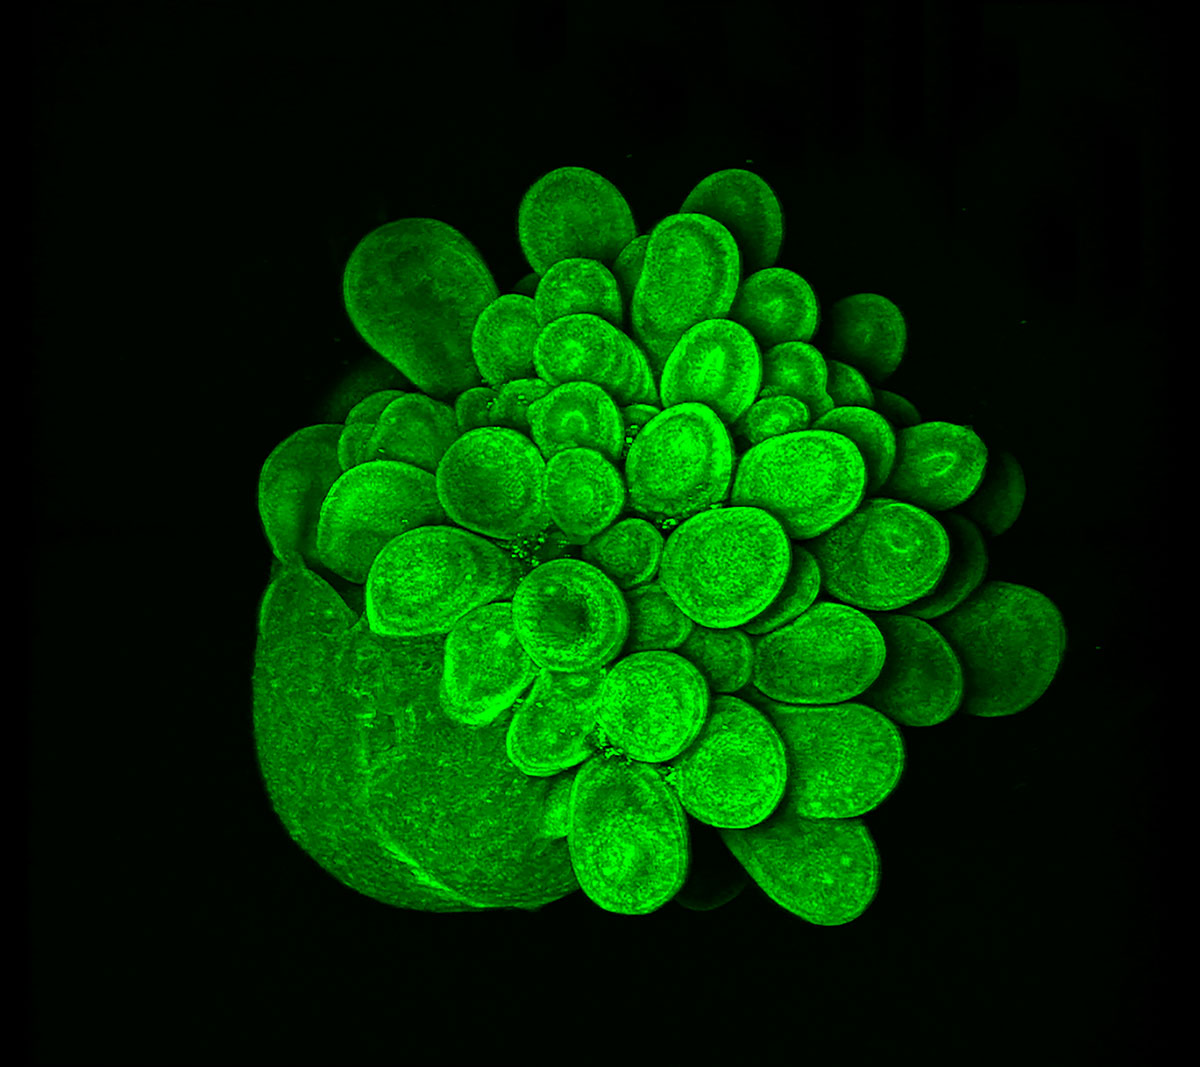

A Blooming Mini Brain

Mariana Oksdath Mansilla

Centre for Cancer Biology

This is an image of a 28 day-old human brain organoid, growing from iPSC that expressed Actin GFP. This 3D culture has a self-organisation of stem cells that mimics the fetal development of the human brain. To culture this organoid, we used a high-content scaffold that we developed in the lab using a 3D printer. The capability to print our high-content device, allows us to test efficiently several scaffold conditions for the growth of human brain organoids. The design of this human brain organoid array that generates healthy cultures (as we can see in the picture), is relevant in the search of a high-throughput platform for the screening of personalised treatment for brain cancer patients.